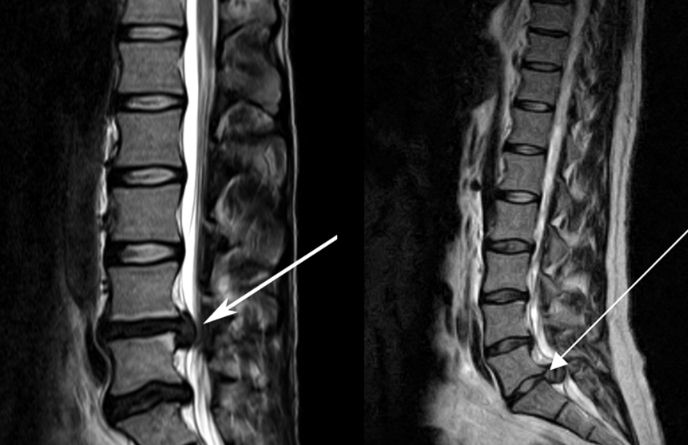

3、核磁共振(MRI):核磁共振沒有輻射,可以多方位成像(橫斷面、冠狀面、矢狀面和斜面),對解剖細節顯示較好,對組織結構的細微病理變化更敏感(如骨髓的浸潤),可以排除神經和脊柱腫瘤等。對于一些落到椎管的髓核組織也不會遺漏?!?/p>